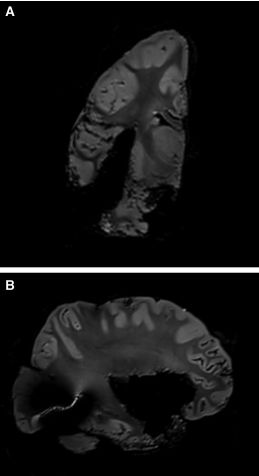

小心切除外囊纤维束,暴露附近的壳核和下额枕束。在导航辅助下,确定术野的每个位点和术腔边界。术后的MRI-T2成像上确认岛叶完全切除,并显示颞上回保留完整(图9)。

图9. 岛叶切除后的MRI- T2成像。A.冠状位显示内镜入路手术通道;B.矢状位确认岛叶完全切除。